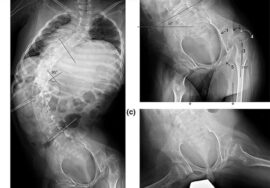

كيفية تشخيص أي مشكلة في العمود الفقري

عند زيارة الطبيب، يتم:

- فحص القوام والظهر

- تقييم التماثل بين الجانبين

- اختبار الانحناء

- طلب أشعة لتحديد درجة الانحناء عند الحاجة